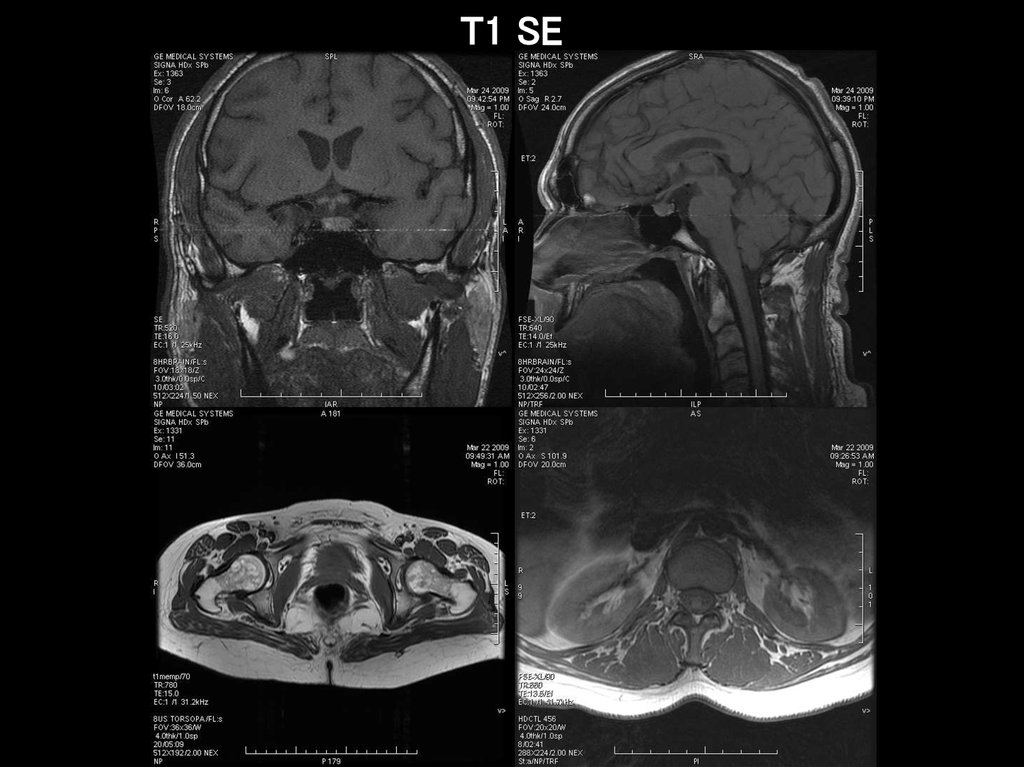

T1 SE

25.